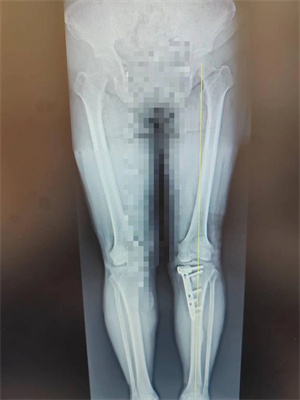

手术团队通过 X 线、CT 等影像学评估,精确计算出下肢力线偏移角度,确定截骨位置及矫正目标;术中采用开放楔形截骨术(OWHTO),在胫骨近端内侧作小切口,借助导向器完成截骨后,撑开骨间隙植入人工骨材料,并用解剖钢板固定,整个过程出血量不足 50ml,耗时约 1 小时,术后患者下肢力线即刻恢复生理曲度;术后第三天,患者便开始部分负重行走,摄片检查显示下肢力线已纠正,结合股四头肌锻炼、关节活动度训练等个性化康复训练,4 周后逐步过渡至完全负重,膝关节疼痛显著缓解,功能恢复良好。

▷术后双下肢全长片,患肢力线已纠正